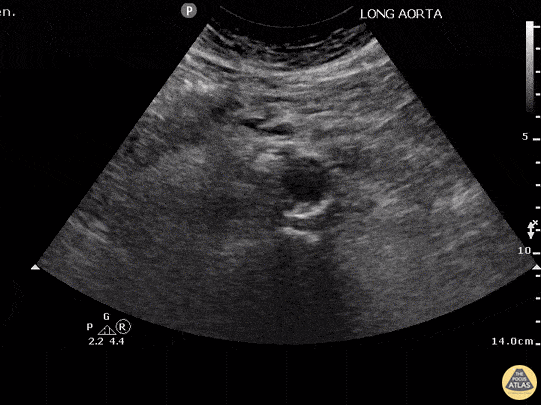

Aortic dissection carries an incredibly high mortality that increases 1%/hour. POCUS can be used as a rule-in test to quickly identify this life threatening diagnosis. If a dissection is not seen on POCUS, CT angiography should still be performed because the sensitivity of POCUS is not as high as for other indications. The spine can be used as a landmark - the echogenic stripe with shadowing in the midline. The aorta is the large vessel anterior and slightly to the right of the spine. In this image an intimal flap can be seen in the anterior third of the aorta consistent with an aortic dissection. The IVC cannot be clearly visualized in this image but would normally be left, less pulsatile, with a less echogenic vessel wall. Non-visualization of the IVC is most often due to bowel gas or compression of the abdomen with the probe. Justin Bowra MBBS, FACEM, CCPU Emergency Physician, RNSH et al.